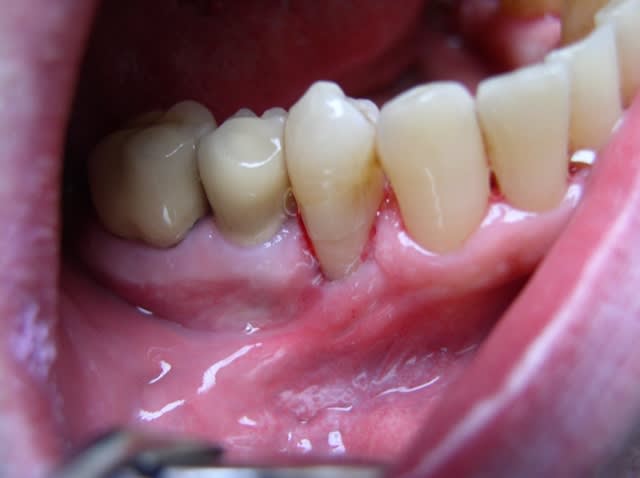

Je préfère personnellement les conjonctifs enfouis. Dans ton cas clinique je me servirais de la gencive attachée présente en vestibulaire de la 45 pour recouvrir mon conjonctif avec un lambeau déplacé latéralement. C'est d'ailleurs ce que j'ai fait dans ce cas très similaire au tien :

Initial thhwv6 - Eugenol

Greffon conjonctif h22esm - Eugenol

Lambeau d plac  lat ralement qmyxvr - Eugenol

Cicatrisation duwhwd - Eugenol